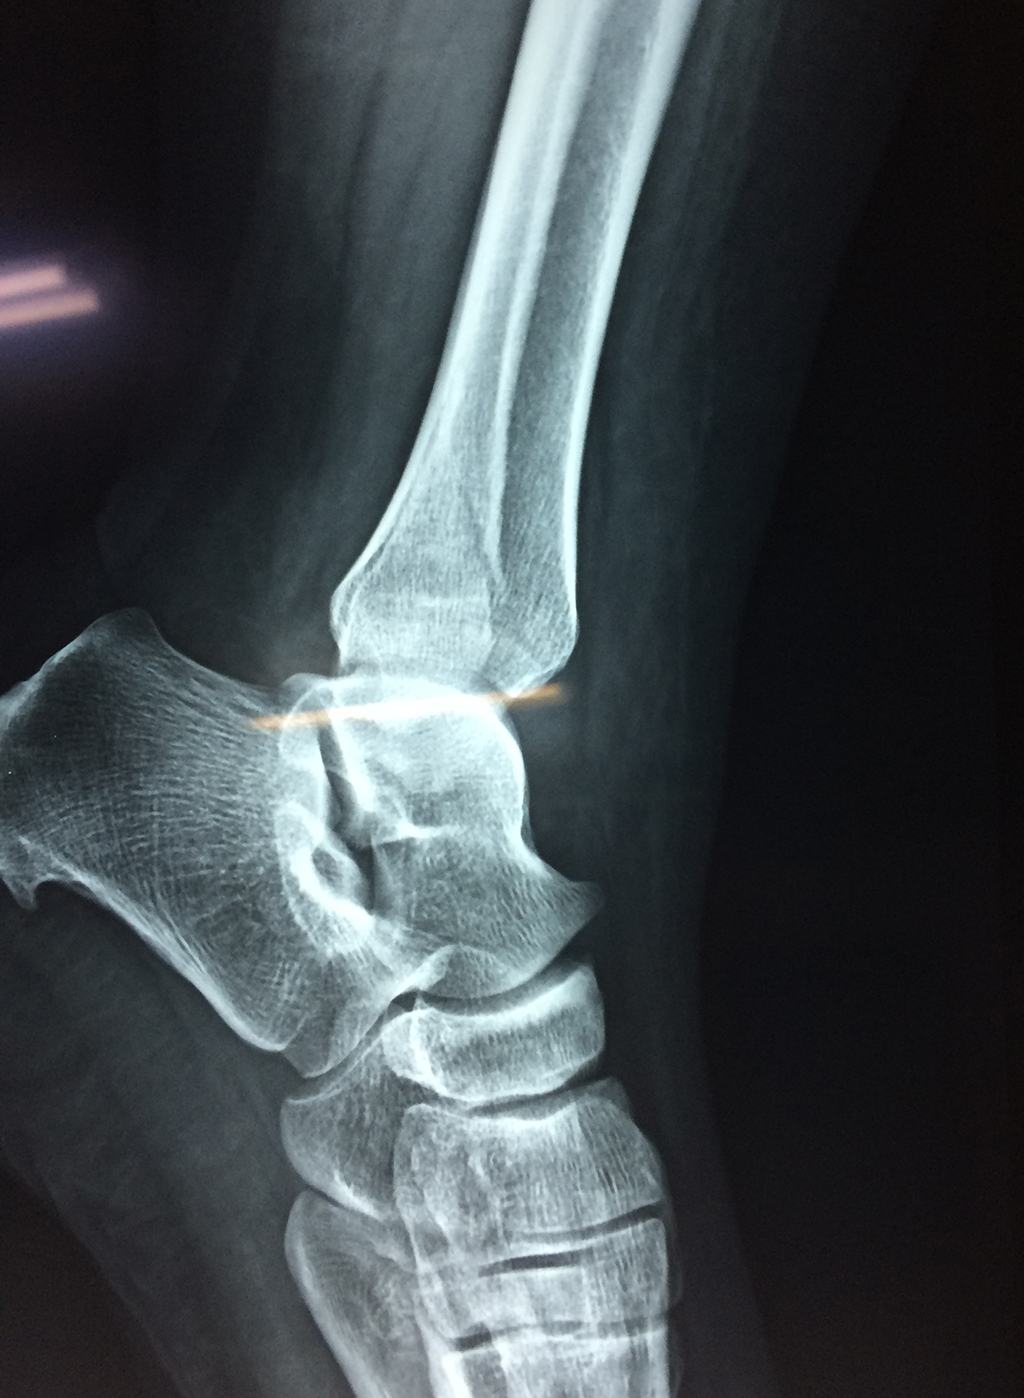

Una fractura de tobillo es la rotura de uno o más de los huesos del tobillo. Estas fracturas pueden ser:

Algunas fracturas de tobillo pueden requerir cirugía si:

- Los extremos de los huesos están desalineados entre sí (desplazados).

- La fractura se extiende hasta la articulación del tobillo (fractura intra-articular).